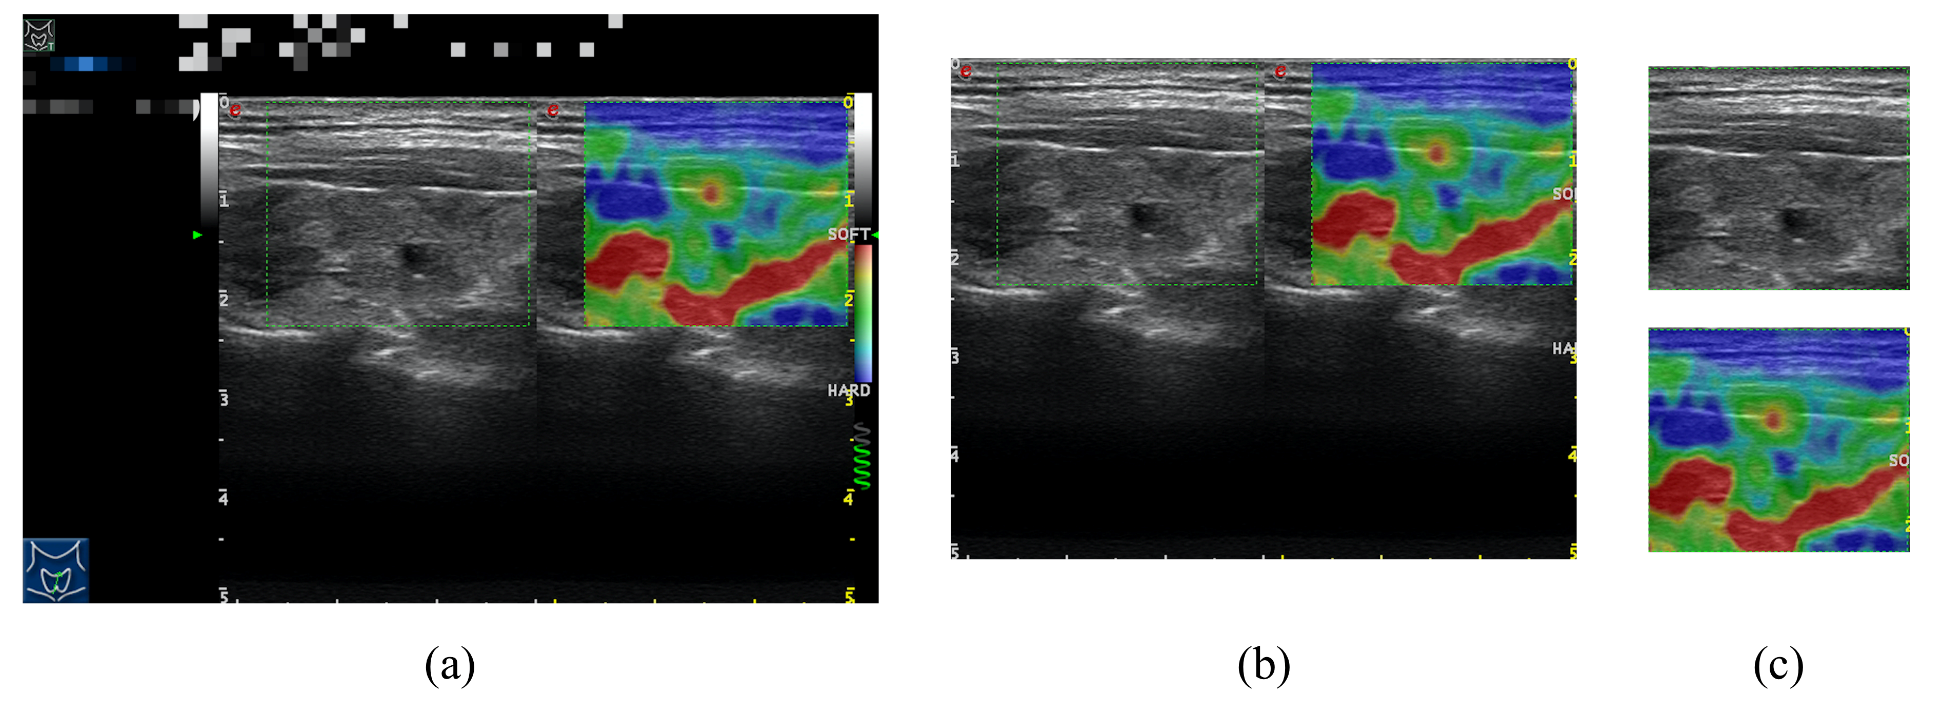

3.1. Visual Comparisons